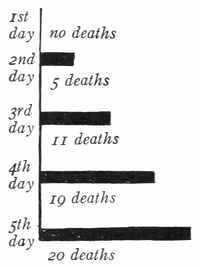

Title: Principles of Public Health

Language: English

Obvious typographical errors and punctuation errors have been corrected after careful comparison with other occurrences within the text and consultation of external sources. Misspellings in the text, and inconsistent or archaic usage, have been retained.